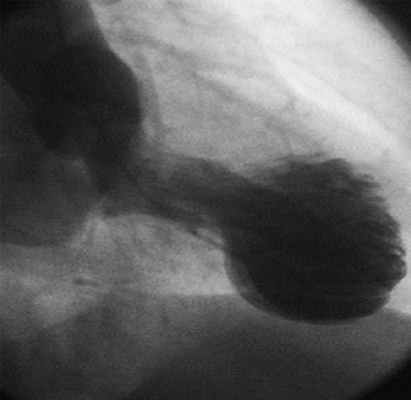

Понятие Кардиомиопатия Такотсубо было представлено кардиологической общественности впервые в 1990г. в Японии, а уже на Конгрессе европейских кардиологов в 2006г. в Барселоне была представлена как самостоятельная назология - как вариант кардиомиопатии. В переводе с японского Takotsubo означает ”ловушка для осьминога”. При данной патологии сердечная мышца расширяется и сердце по своей форме становится похожей на сосуд (кувшин для вина). рис.1

Рис.1.”Ловушка” для осьминонов.

ЭХОКГ выявляет акинез или дискинез верхушечных и/или средних сегментов ЛЖ, гиперкинез базальных сегментов ЛЖ, вследствие чего возможна, также, обструкция выносящего тракта ЛЖ, сегментарное либо тотальное расширение полости ЛЖ, снижение ФВ ЛЖ от 50% в течение 4-8 недель. (Рис. 4).

Рис. 4. Двухмерная ЭХОКГ-картина Takotsubo кардиомиопатии.

Коронароангиография выявляет отсутствие гемодинамически значимых сужений коронарных артерий, вентрикулография выявляет полиморфизм движения стенок ЛЖ в фазы наполнения и опорожнения (Рис.5.)

Рис.5. Вентрикулография при Takotsubo кардиомиопатии.